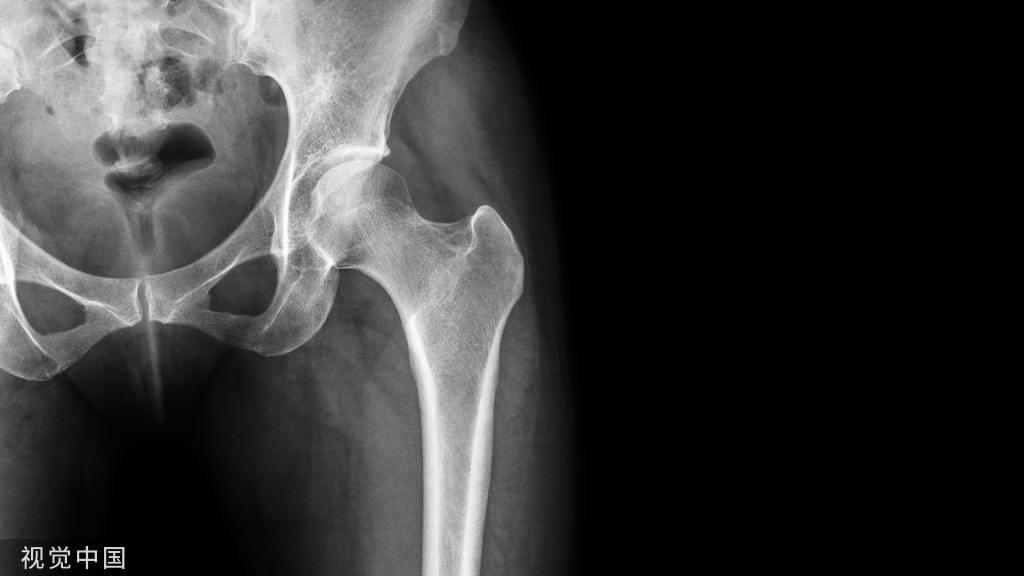

病例1:L5-S1左侧复发椎间盘突出